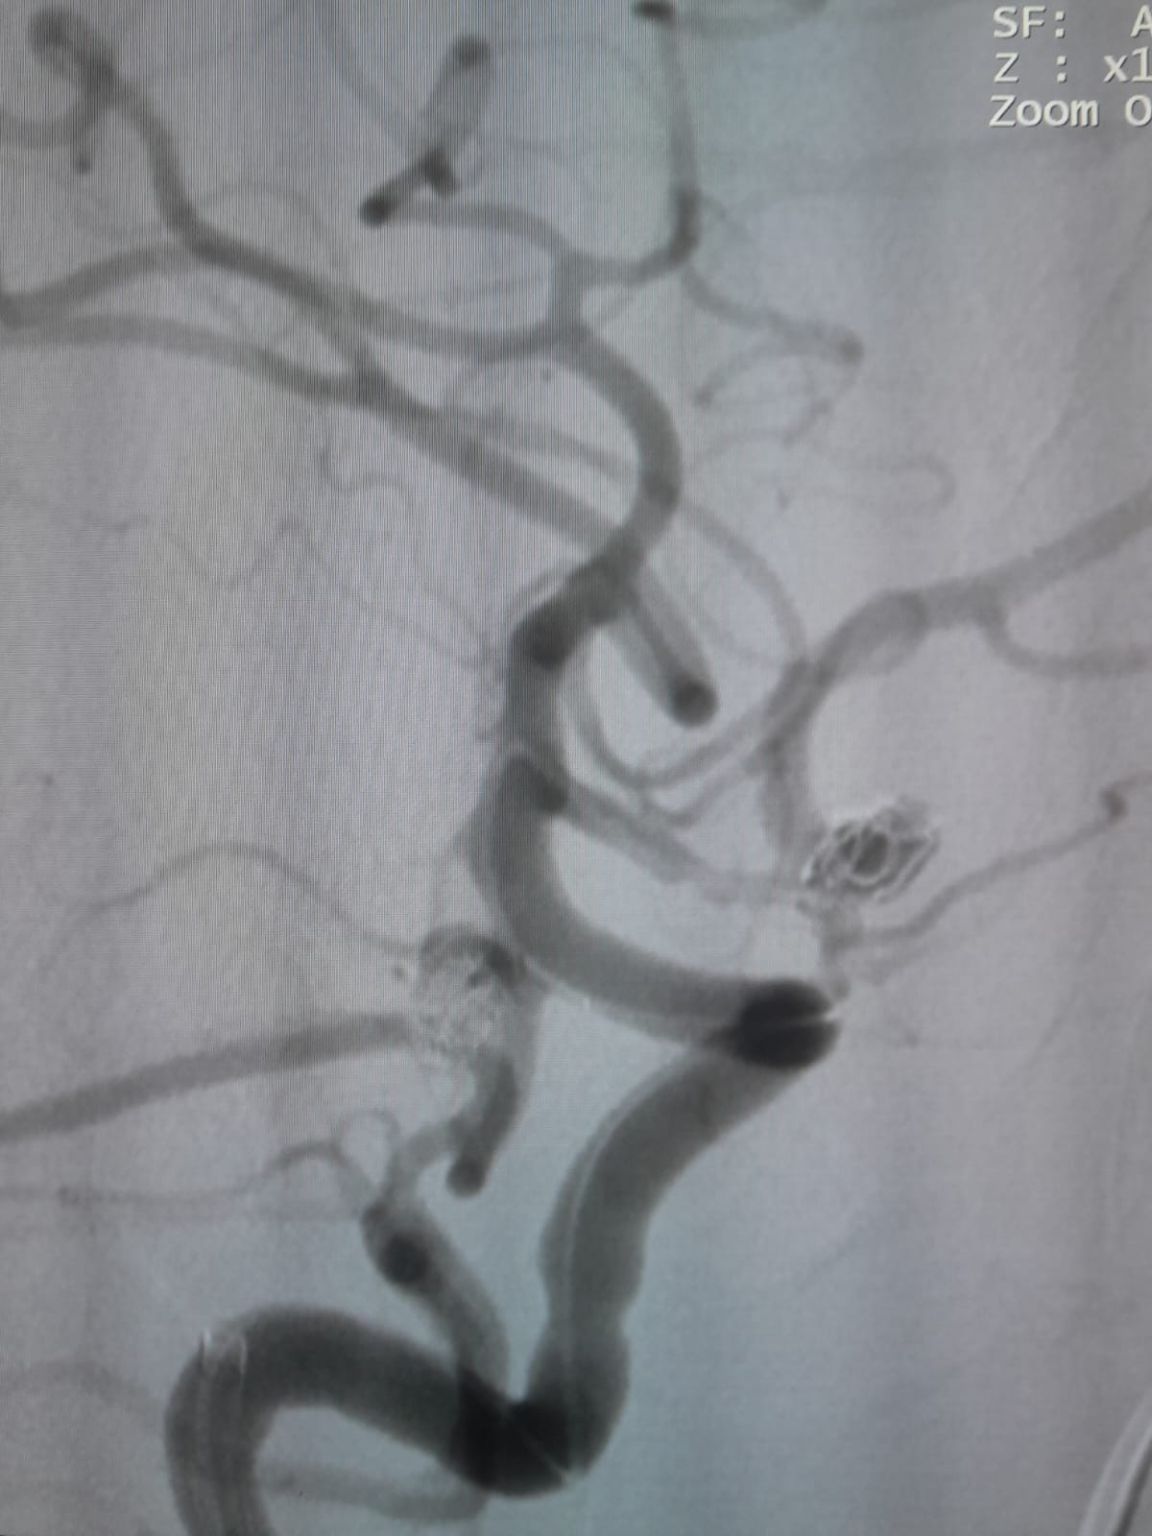

患者は、以前にコイル塞栓症で治療された、新たに発見された前伝達動脈 (AComA) 嚢動脈瘤と後伝達動脈 (PComA) 動脈瘤と診断されました。 追跡画像では、PComA動脈瘤の残留充填が明らかになり、追加の介入が必要でした。

前部通信動脈動脈瘤

血管へのアクセスが確立され、チームはフリーパスのナビゲートに成功しました®ターゲット部位への使い捨てマイクロカテーテル (TJMC14)。 塞栓は3つのPerdenserを使用して行われました®デロンパーと共に展開された塞栓コイルシステム (TJCST4.508-3D、TJCST0306-3D、TJCST0206-3D)®コイルの取り外しのコントローラー (TJCDC)。